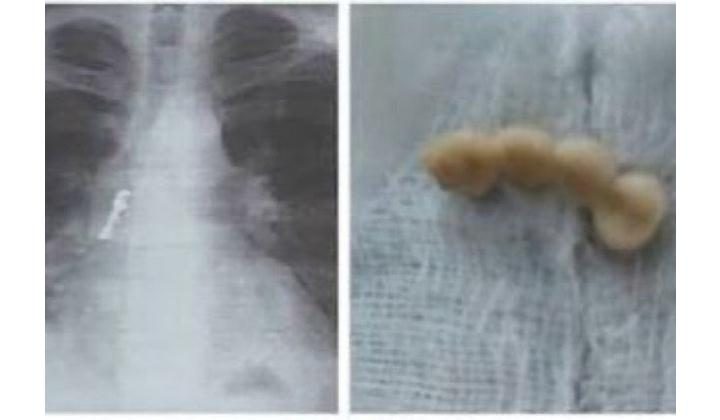

Врачи провели мужчине фибробронхоскопию, после чего установили, что зубной мост находится в промежуточном бронхе правого легкого, где начался активный воспалительный процесс, который мог привести к пневмонии, разрыву стенки бронха с пневмотораксом или гнойному бронхиту.

Через канал бронхоскопа медики провели петлю, захватили коронки, зафиксировали и извлекли.